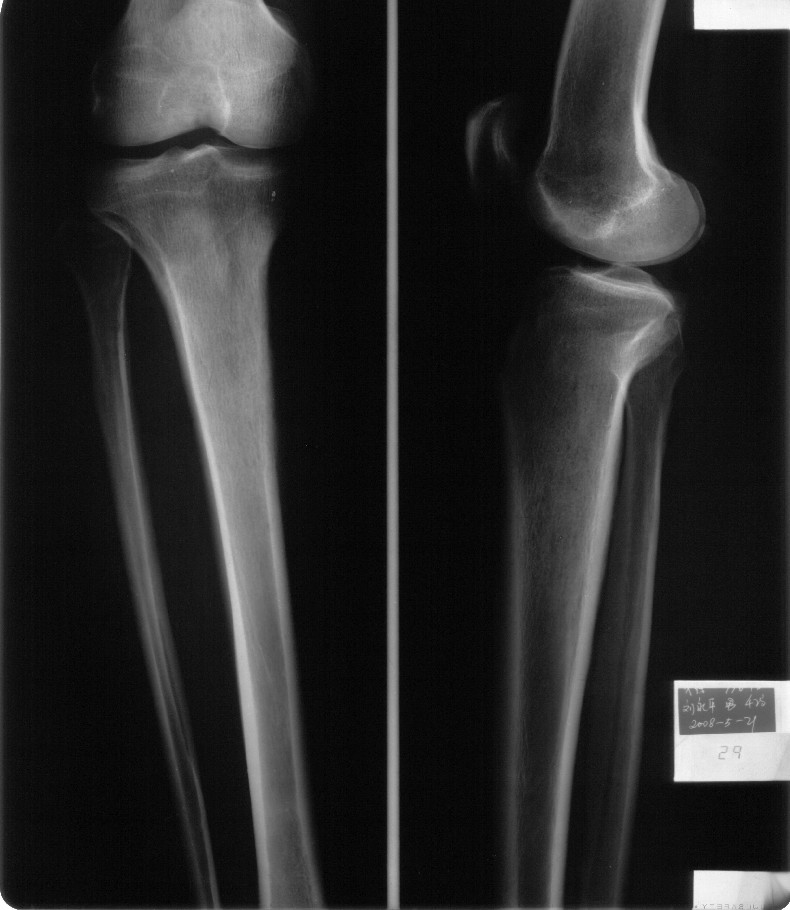

男,42岁。4个月前钢筋钝伤右侧小腿部,当时因无明显外伤,未引起重视。一周后因受伤腿部疼痛,发现肿胀,随后到当地医院进行检查(2008年4月16日)。因未发现骨质异常未引起重视,仅仅进行口服抗生素治疗处理。经过一段时间治疗但未见明显治疗效果在5月29日又进行x线检查,发现有胫骨密度上段密度增高,又进行抗炎治疗,仍未见效果。又在7月3日进行x线检查,仍然报告有胫骨上端密度增高,并建议ct检查。以下是相关检查结果:

髓腔密度呈絮状增高,胫骨上端内侧可见层状骨膜反应,考虑骨髓炎.

髓腔密度呈絮状增高,胫骨上端内侧可见层状骨膜反应,肌间隙模糊,考虑骨髓炎.